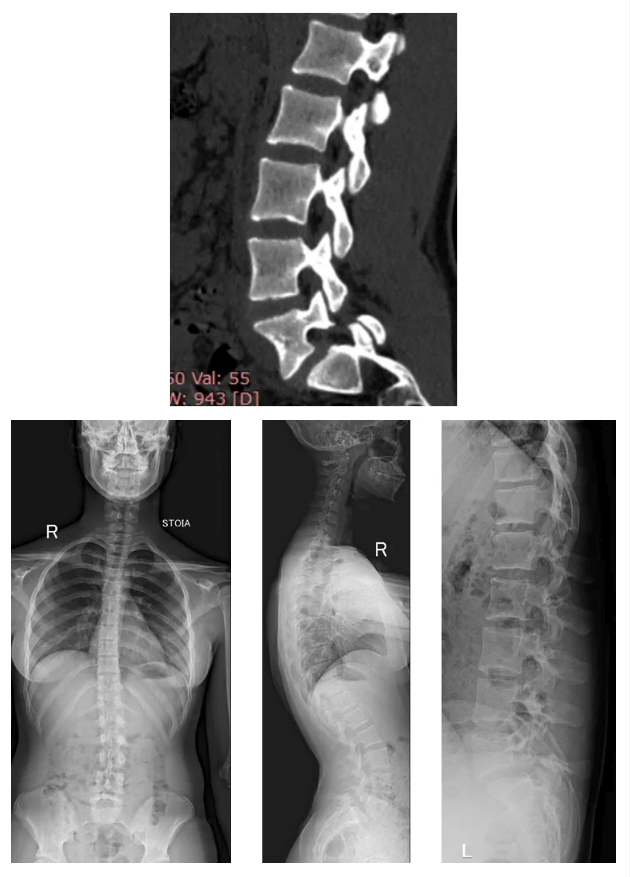

Девочка с детства занималась гимнастикой, но в последнее время ее стали беспокоить сильные боли в поясничном отделе и тянущие боли в икроножных мышцах. Дополнительные обследования уже в Клинике патологии позвоночника и редких заболеваний Центра Илизарова показали, что на фоне основного заболевания, дефицита щелочной фосфатазы сформировались характерные остеопатии, а также двусторонний спондилолиз.

Операцию проводили руководитель Клиники патологии позвоночника и редких заболеваний, к.м.н. Алексей Евсюков и врач-вертебролог отделения №9, к.м.н. Полина Очирова. Вмешательство выполнили в два этап. Первым выполнили передний спондилодез, установили кейдж. Вторым этапом выполнили транскутанный спондилосинтез с последующей фиксацией.